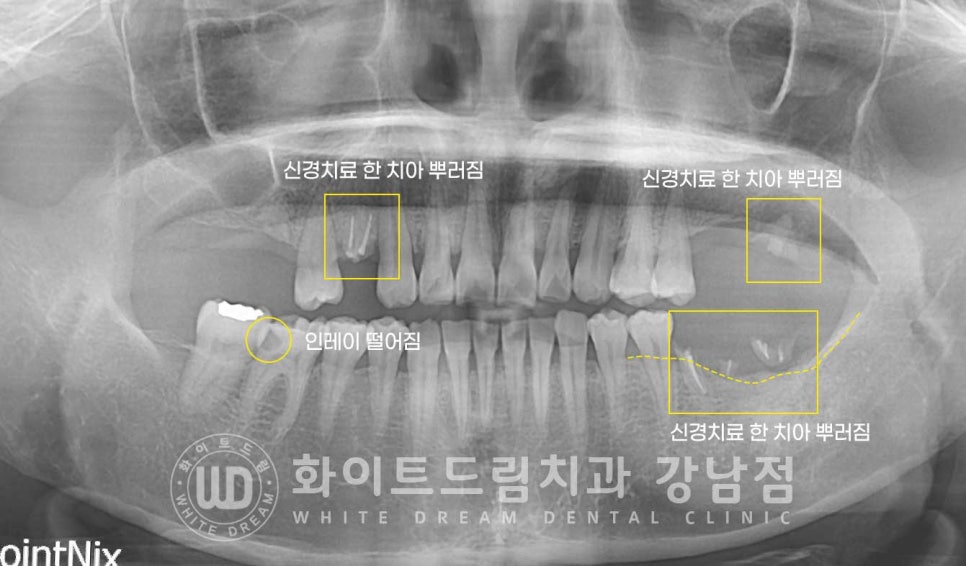

환자분의 초진 구내 상태입니다.

16,17번 치아는 상실된 상태이고

14, 27, 36,37번 치아가 뿌리만 남아있는 상태입니다.

뿌리만 남아있는 치아들은 모두 신경치료를 받은 흔적이 보이는데

신경치료 후 크라운을 씌우지 않으셨고,

있던 크라운도 시간이 지나면서 탈락된 상태로 방치를 하셔서

치아가 모두 저작력을 버티지 못하고 부러져버린 상태인 것이죠.

뿌리만 남아있는 치아들은 모두 발치 후 임플란트를 식립하기로 하였고

하악 46번 인레이가 떨어진 치아는 신경치료 후 크라운치료를 진행하기로 했습니다.

▲ 46번 인레이가 떨어진 치아 부위, 신경이 겉으로 노출되어 있는 상태여서 신경치료를

진행하게 되었습니다.